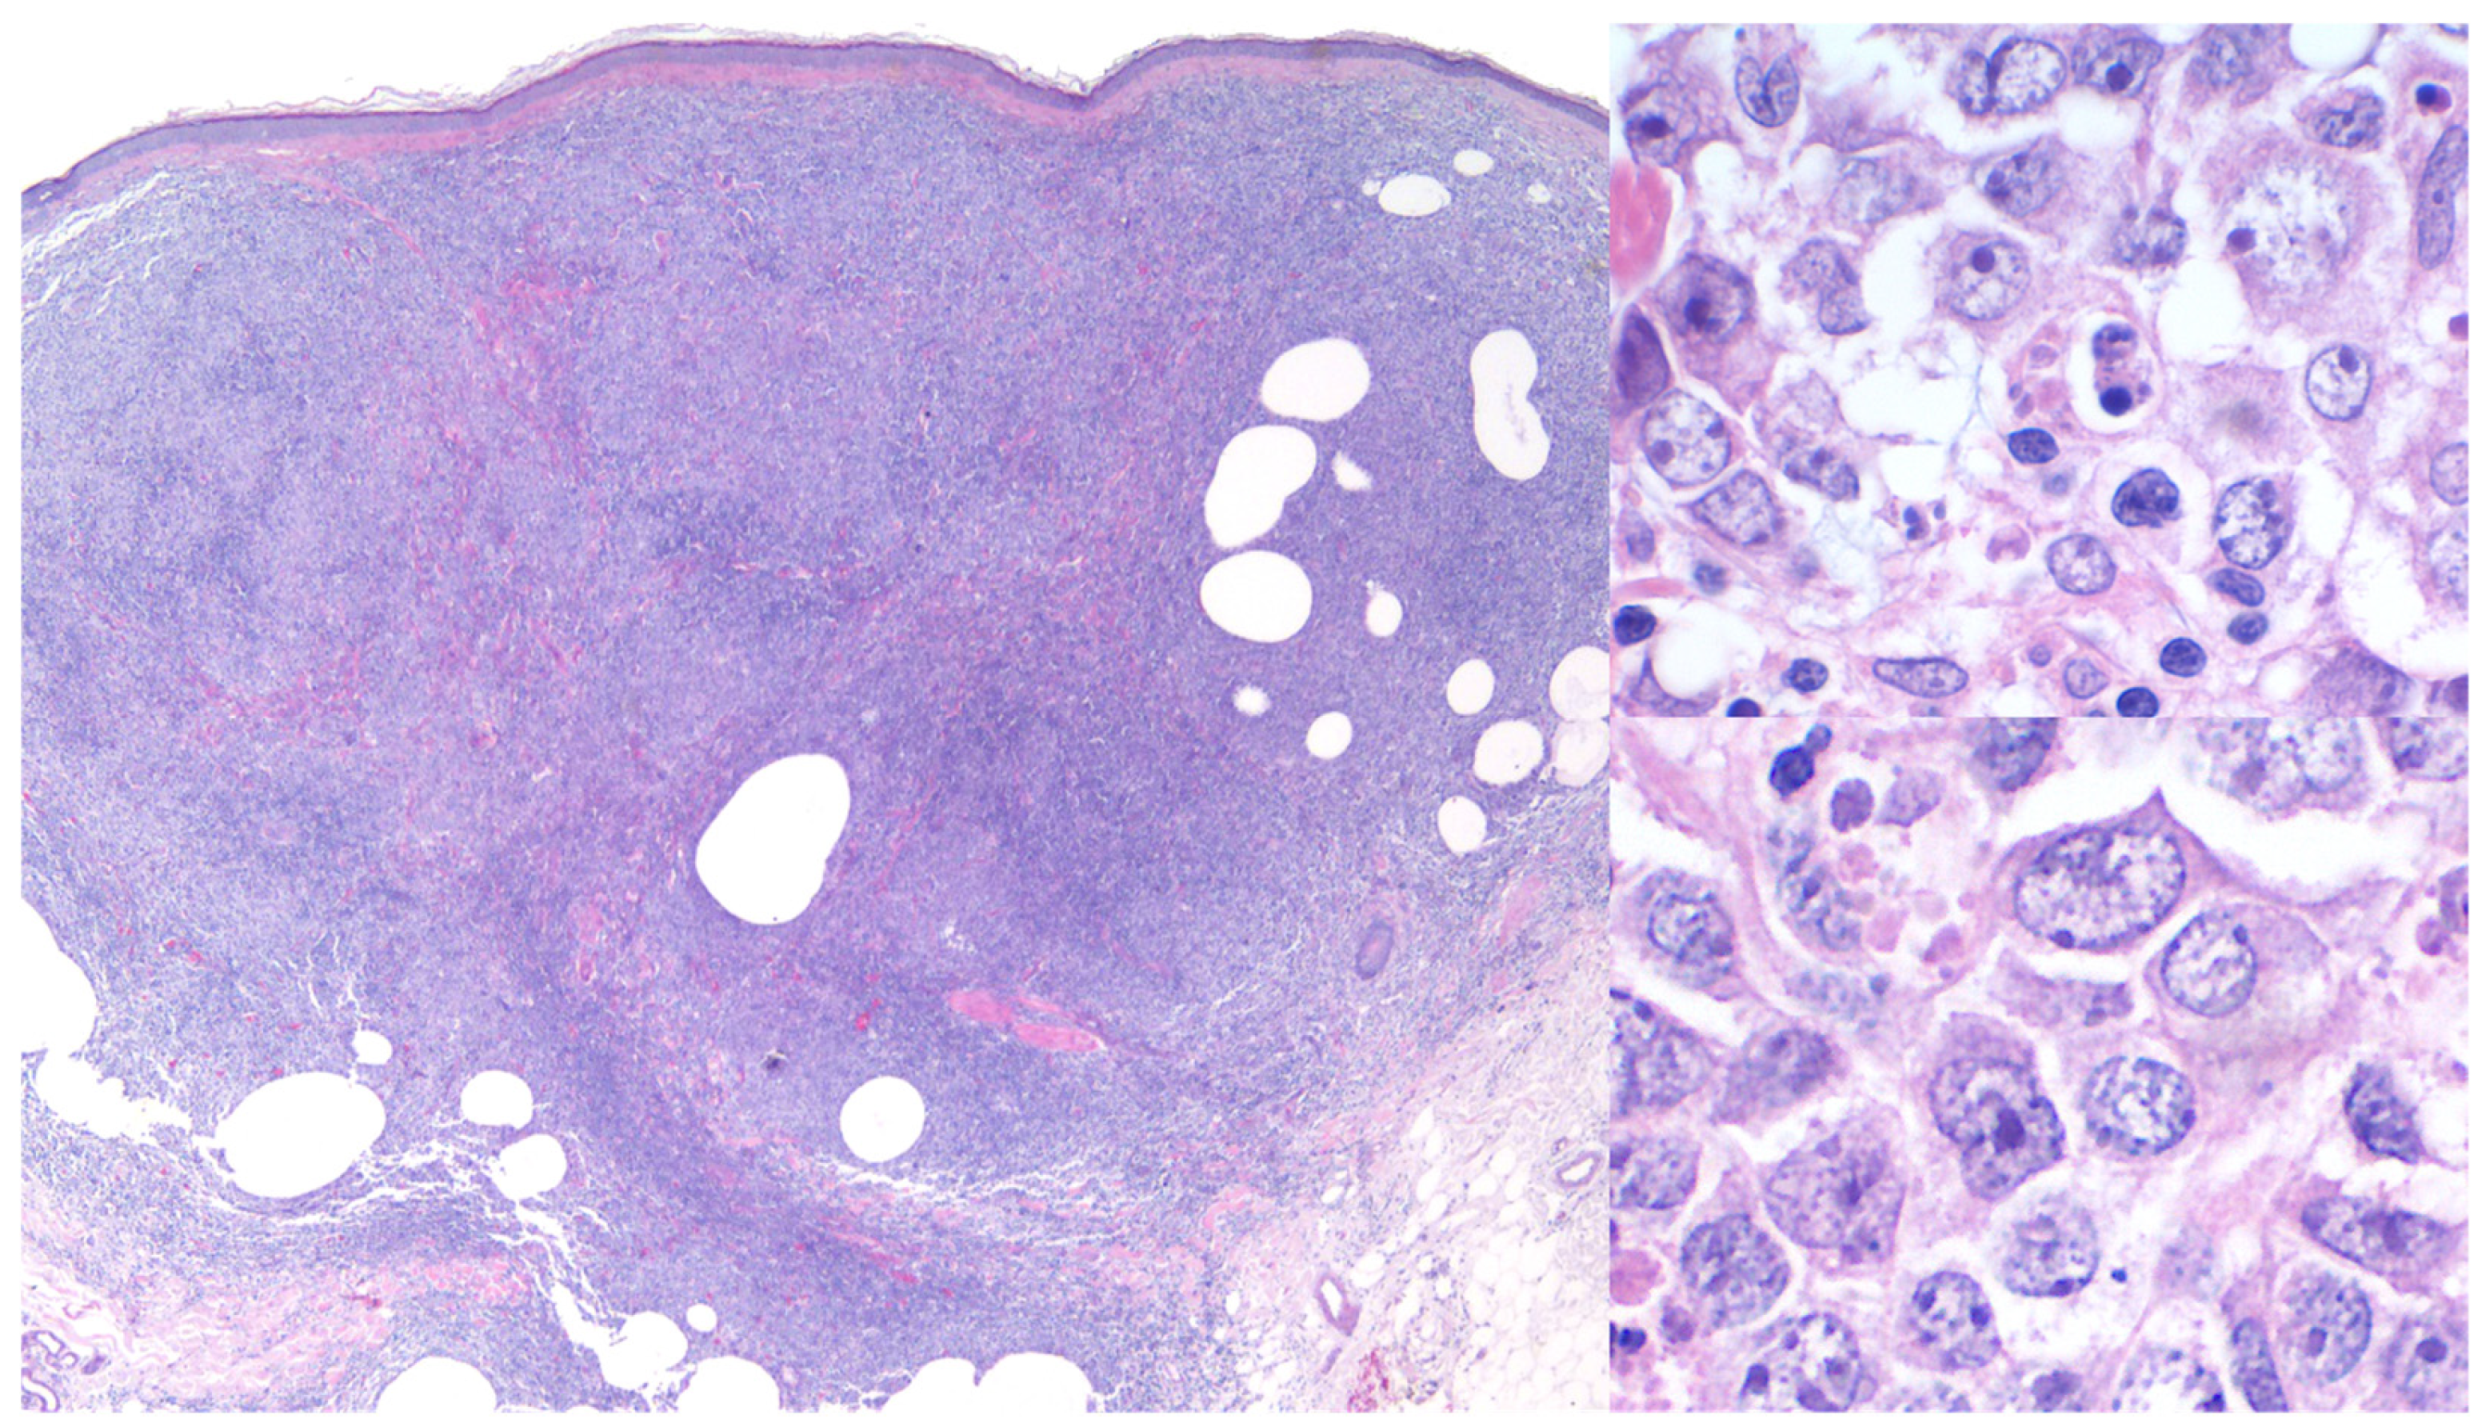

3.1. Primary Cutaneous Diffuse Large B-Cell Lymphoma, Leg Type (PCDLBCL,LT)

3.3. Differential Diagnosis for PCDLBCL,LT